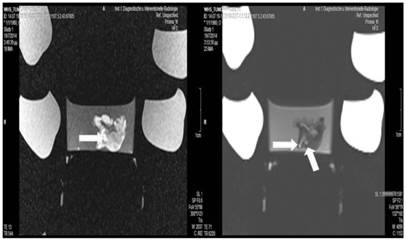

Figure 5

Lipiodol group; T1 sequence: Heterogeneous appearance in the central part of the tumor, low intensity indicates necrosis. T2 sequence: High signal intensity indicates necrosis. White and black arrows indicate lipiodol solution within the tumor. Necrosis is not extensive as presented in the current figures.

Tumor necrosis and apoptosis were the major purposes of our study. Survival was also recorded. Our records and MRI findings indicate that a major toxicity was observed in the group where cisplatin, lipiodol and microwave were applied. None of the animals survived more than a week. Moreover; hemorrhage apart from necrosis was observed inside the tumors. Survival was the following for the groups: microwave (25days) ≥ cisplatin (22 days) > control (20 days) > lipiodol (16 days)> microwave plus lipiodol (16 days) > cisplatin plus lipiodol (12) > cisplatin plus microwave (12 days) > lipiodol plus cisplatin plus microwave (5 days). (Figure 5-12.)